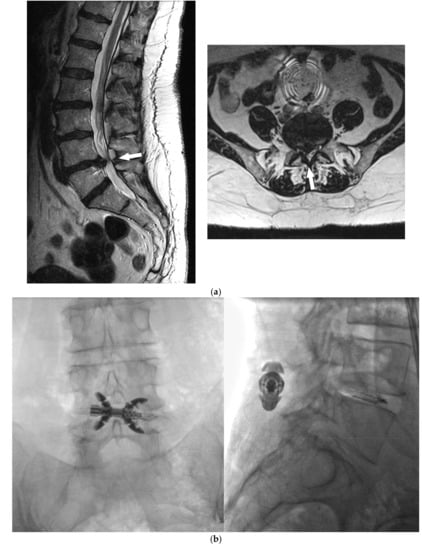

- Bonaldi, G.; Bertolini, G.; Marrocu, A.; Cianfoni, A. Posterior vertebral arch cement augmentation (spinoplasty) to prevent fracture of spinous processes after interspinous spacer implant. AJNR Am. J. Neuroradiol. 2012, 33, 522–528. [Google Scholar] [CrossRef]

- Manfré, L. Posterior Arch Augmentation (Spinoplasty) before and after Single and Double Interspinous Spacer Introduction at the Same Level: Preventing and Treating the Failure? Interv Neuroradiol. 2014, 20, 626–631. [Google Scholar] [CrossRef]